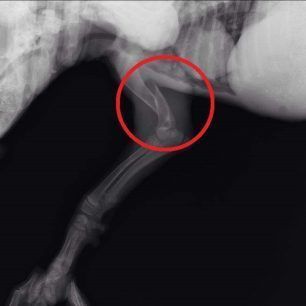

Το κουταβάκι που βλέπετε στις φωτογραφίες εντοπίστηκε χθες στο Άκτιο να κλαίει από τους πόνους κοντά στα διόδια της υποθαλάσσιας σήραγγας καθώς όπως αποδείχτηκε έχει σπασμένα τα δύο πόδια του ενώ είναι χτυπημένο και στην κοιλιά. Το πως τραυματίστηκε το ζώο παραμένει άγνωστο αν και σύμφωνα με τον κτηνίατρο Νίκο Ρώσσο, που το εξέτασε, κάποιος είναι πολύ πιθανό να το το κλώτσησε.

Η Δώρα Τσάτση μέλος του σωματείου «Παρέμβαση για τα Ζώα - Πρέβεζα» εξήγησε στο www.zoosos.gr ότι ο κ. Ρώσσος τους είπε πως είναι απίθανο το κουταβάκι, που ζυγίζει μόλις τέσσερα κιλά, να χτυπήθηκε από όχημα καθώς δεν έχει σημάδια και αυτά τα τραύματα προκαλούνται μόνο από κλωτσιά.

Εξαιτίας του νεαρού της ηλικίας του κουταβιού δεν θα γίνουν όλες οι επεμβάσεις ταυτόχρονα. Αρχικά θα χειρουργηθεί στην κοιλιά και στην συνέχεια θα ακολουθήσουν οι επεμβάσεις στο πίσω πόδι του που έχει σπάσει σε δύο σημεία και στη συνέχεια στο μπροστινό.